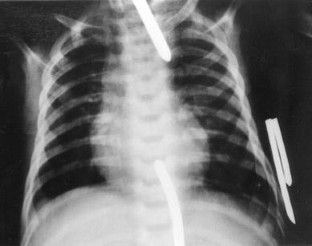

Fig. 1